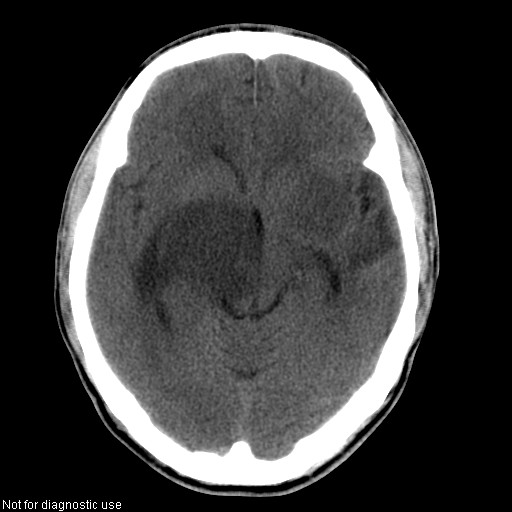

以下是引用hhcckk在2008-1-26 16:03:00的发言:[br]考虑病毒感染可能性大[br]1、病人发病时间短,1周,转移病灶时间长[br]2、楼主虽然没有告诉我们年龄,但从颅内情况来看,病人年纪不会很大,脑池,脑沟不是很明显,当然,可能有脑肿胀的原因,转移灶病人年纪一般较大[br]3、从病灶特点来看,转移多发生在灰白质交界区,多有指状水肿,占位效应明显,此病人呈对称性发布,发生在脑实质深部,与转移有所区别[br]4、病人经抗炎,止咳效果不好,可能是病毒感染,抗生素治疗效果不好[br]5、建议楼主1、增强 2、有呼吸系统的症状何不拍个胸片